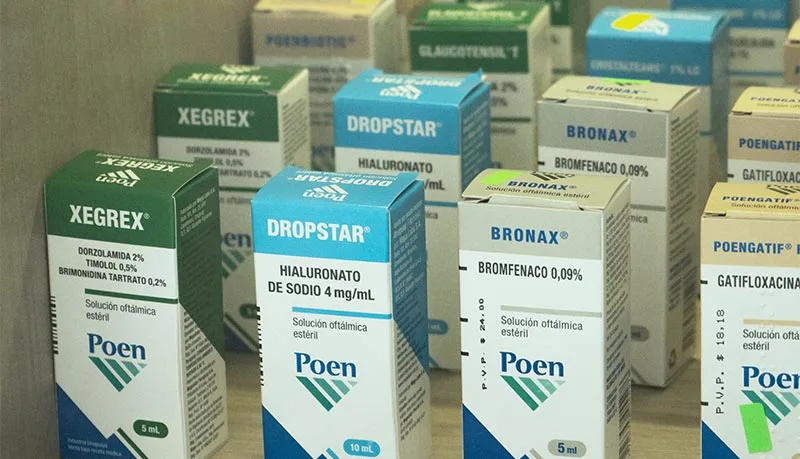

Farmacia Especializada